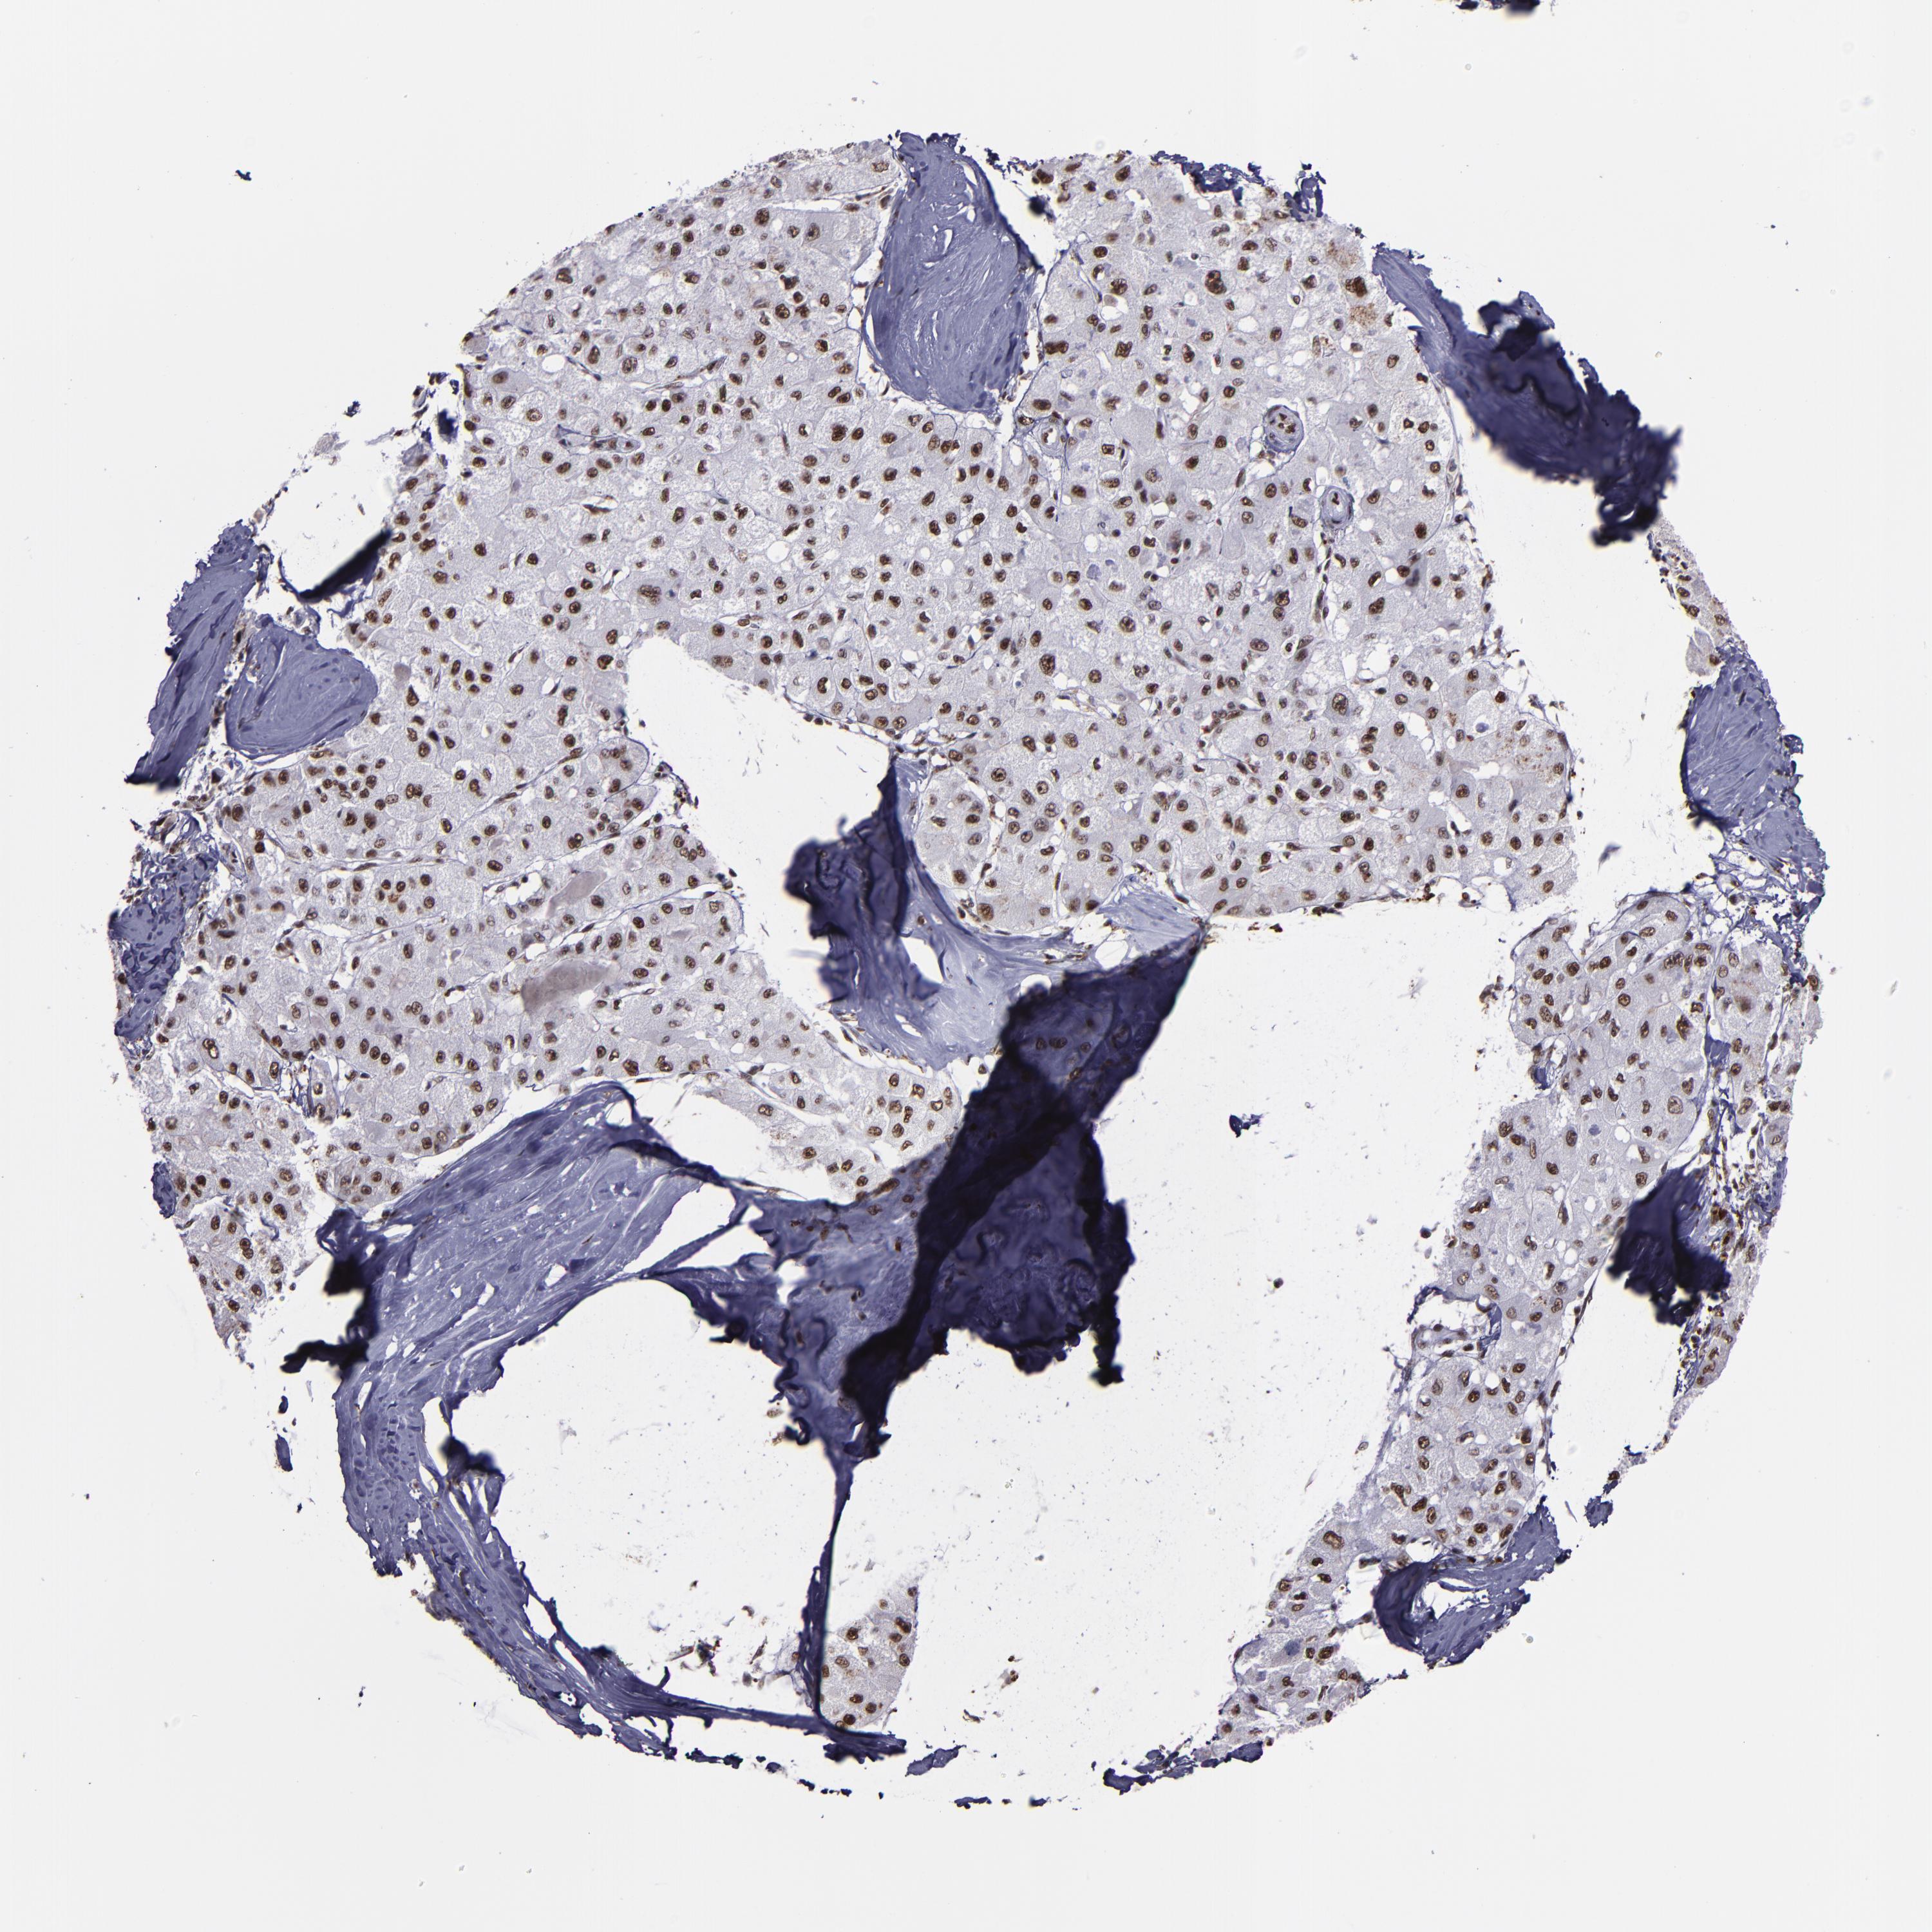

LIVER CANCER - Protein expressioni

A mouse-over function shows sample information and annotation data. Click on an image to view it in a full screen mode. Samples can be filtered based on level of antibody staining by selecting one or several of the following categories: high, medium, low and not detected. The assay and annotation is described here.

Note that samples used for immunohistochemistry by the Human Protein Atlas do not correspond to samples in the TCGA dataset.

Antibody stainingi

Antibody staining in the annotated cell types in the current human tissue is reported as not detected, low, medium, or high, based on conventional immunohistochemistry profiling in selected tissues. This score is based on the combination of the staining intensity and fraction of stained cells.

Each image is clickable and will lead to virtual microscopy that enables deeper exploration of all samples and also displays staining intensity scores, fraction scores and subcellular localization as well as patient and tissue information for each sample.

Antibody HPA002568

Staining

High

Medium

Low

Not detected

Intensity

Strong

Moderate

Weak

Negative

Quantity

>75%

75%-25%

<25%

None

Location

Nuclear

Cytoplasmic/membranous

Cytoplasmic/membranous,nuclear

Cholangiocarcinoma

Carcinoma, Hepatocellular, NOS